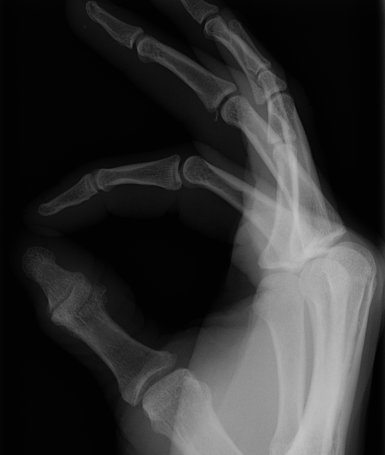

Return to Volar Plate Fracture